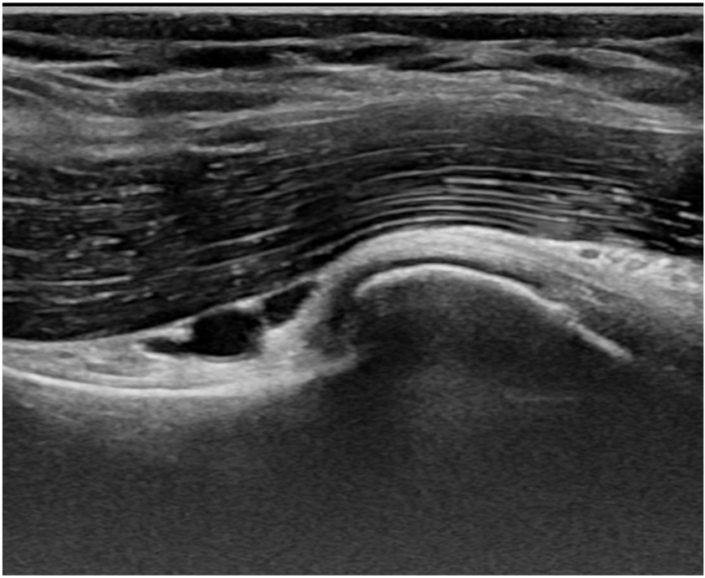

Echografie

Bij het SchouderHuis maken we naast lichamelijk onderzoek gebruik van echografie. Je kunt met echografie sterke aanwijzingen vinden voor slijtage. We overleggen met de huisarts of het maken van röntgenfoto’s dan nog nodig is. Als de schouder zoveel klachten geeft dat je meer hulp nodig hebt dan fysiotherapie kan bieden, dan word je doorgestuurd naar de orthopedisch chirurg.